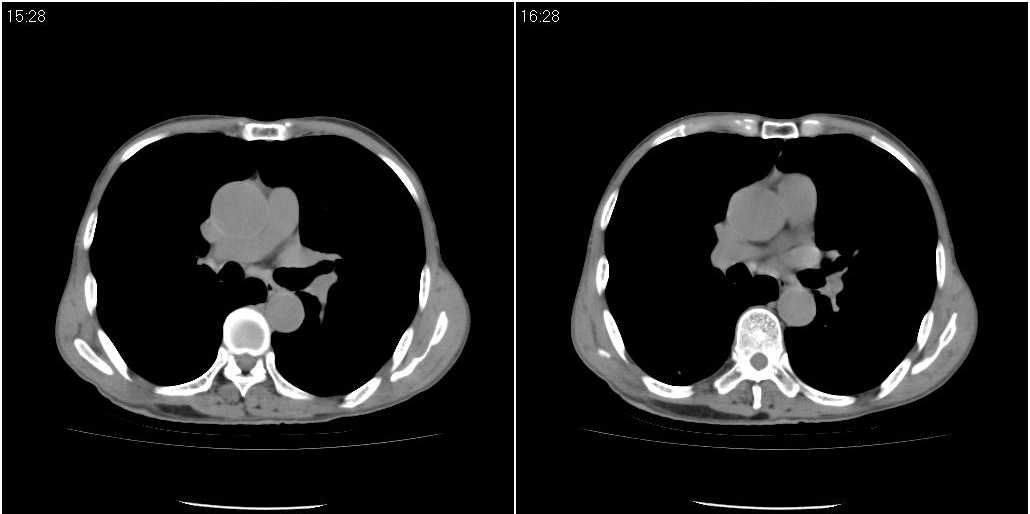

1)右肺中叶慢性炎症并支气管扩张,节段性肺不张。2)两肺下叶支气管扩张。